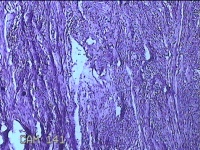

子宫肌瘤

性别

女

年龄

38岁

临床诊断

一般病史

发现子宫肌瘤复发7年余。

标本名称

大体所见

灰白粉红色结节样肿物8.5x5.5x4cm一个,表面糜烂,切面灰白色,编织状,质中。

富于细胞性平滑肌瘤

考虑富细胞平滑肌瘤。

组织处理和染色都不太理想。